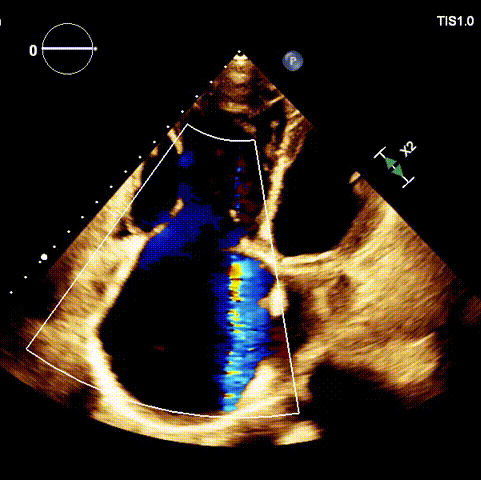

1.二尖瓣位機(jī)械瓣位置及功能未見異常;2.雙房及右室明顯擴(kuò)大(左房收縮容積115ml,右房收縮容積370ml,右室中段左右徑65mm,右室FAC37%),下腔靜脈及冠狀靜脈竇擴(kuò)張(下腔靜脈直徑44mm,冠狀靜脈竇直徑22mm);3.極重度三尖瓣反流(FTR 6+)。

術(shù)前超聲